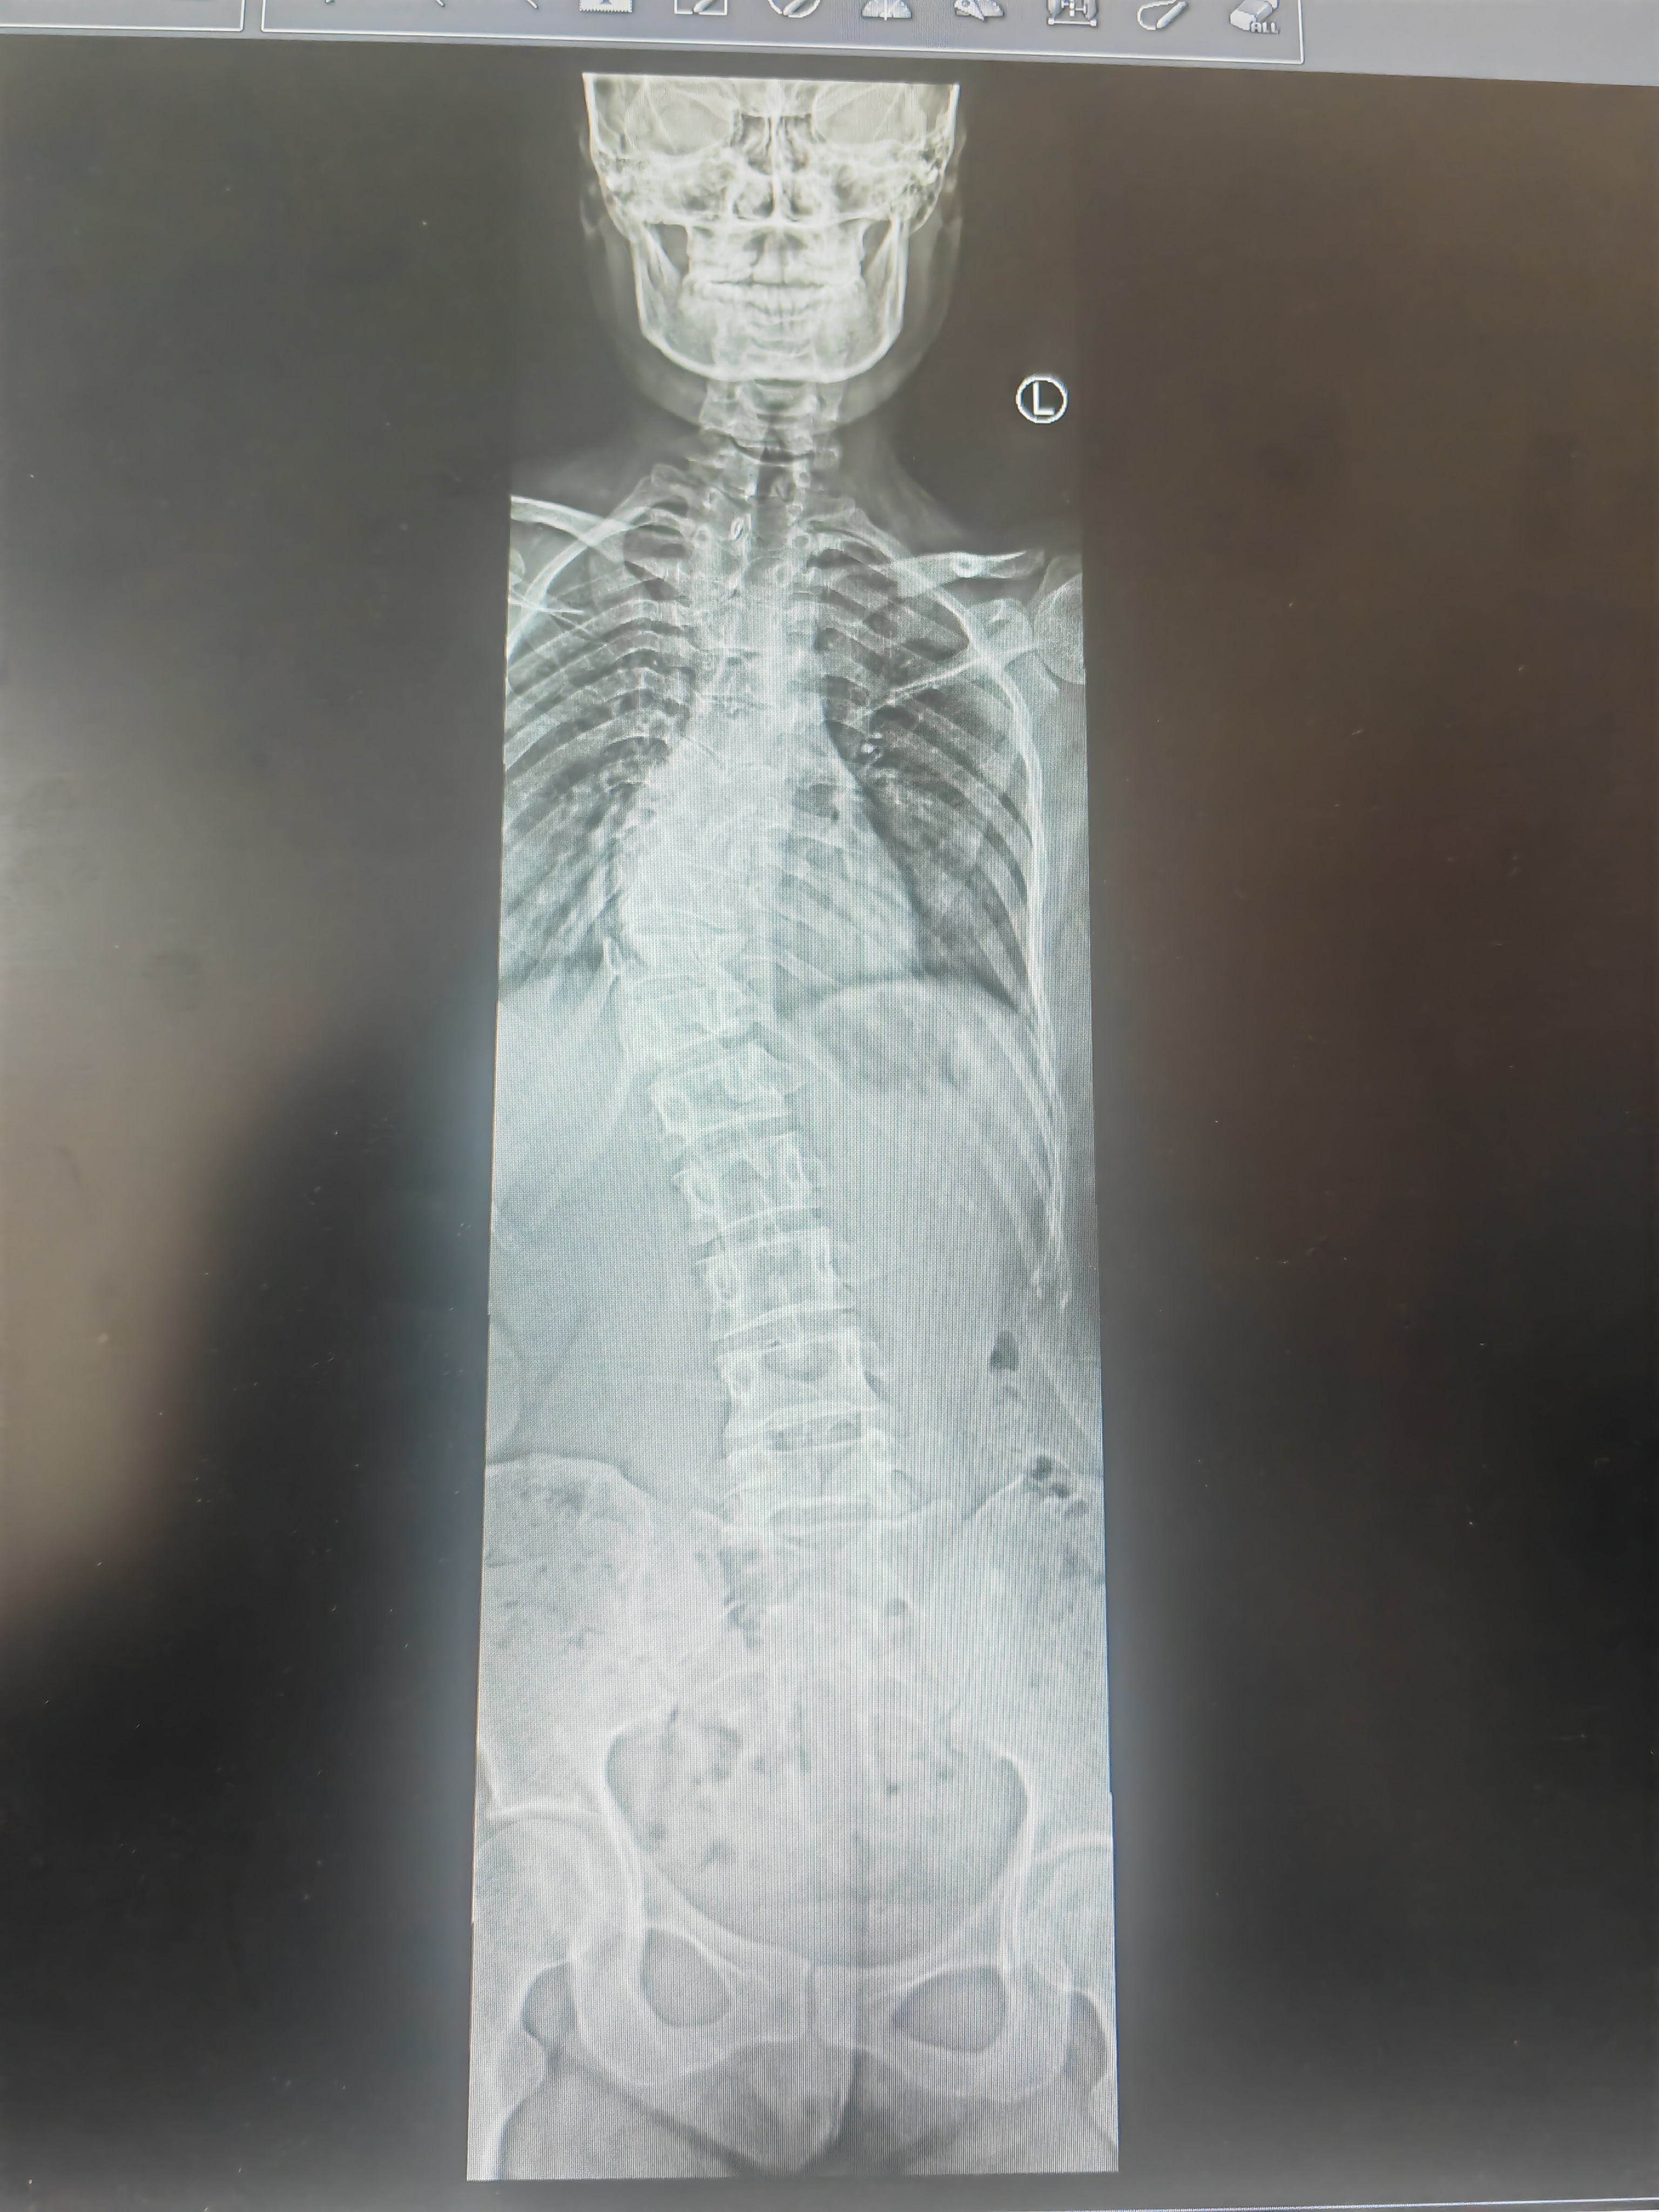

脊柱侧弯申请智善救助QQ③群

脊柱侧弯申请智善救助QQ③群:737257297